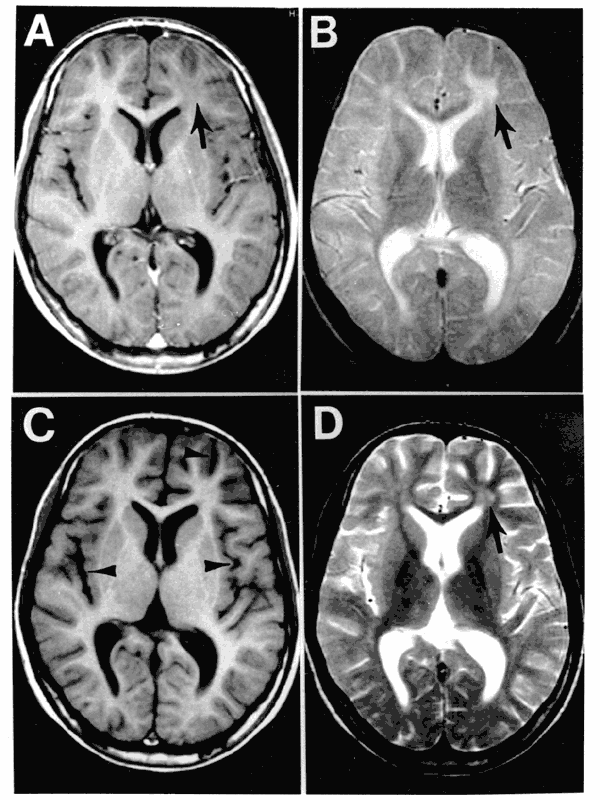

Magnetic resonance imaging (MRI) identifies plaques (areas of white matter demyelination) associated with multiple sclerosis (MS).

Gross inspection of brains with multiple sclerosis (MS) reveal white matter plaques that appear gray.

- Hemiparesis is a loss of sensation to one side (cerebral white matter, usually periventricular)